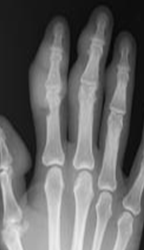

Fig 32 B. Artropatía por gota.

Rx AP: Cambios inflamatorios de los dedos, en relación con las articulaciones interfalángicas.